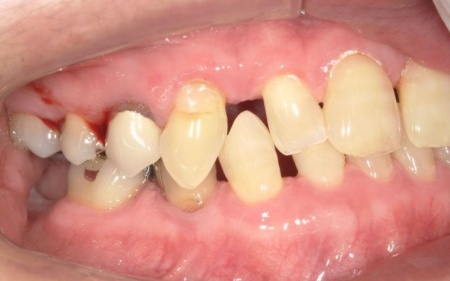

70代女性 歯根が割れた左下奥歯を抜きインプラントで噛み合わせを回復させた症例

「噛んだときに左下奥歯が痛むので診てほしい」とご相談いただきました。

レントゲン撮影を行って詳しく拝見したところ、左下奥歯(第1小臼歯)の歯根が割れていました。

このまま放置すると、周囲の骨や歯茎に細菌感染が広がるリスクがあります。

まず、周辺組織に負担をかけないよう配慮しながら、慎重に左下奥歯(第1小臼歯)を抜きます。

抜歯後は骨や歯茎の回復を待ち、口腔内の状態が安定したことを確認して、インプラント埋入手術へ進みました。